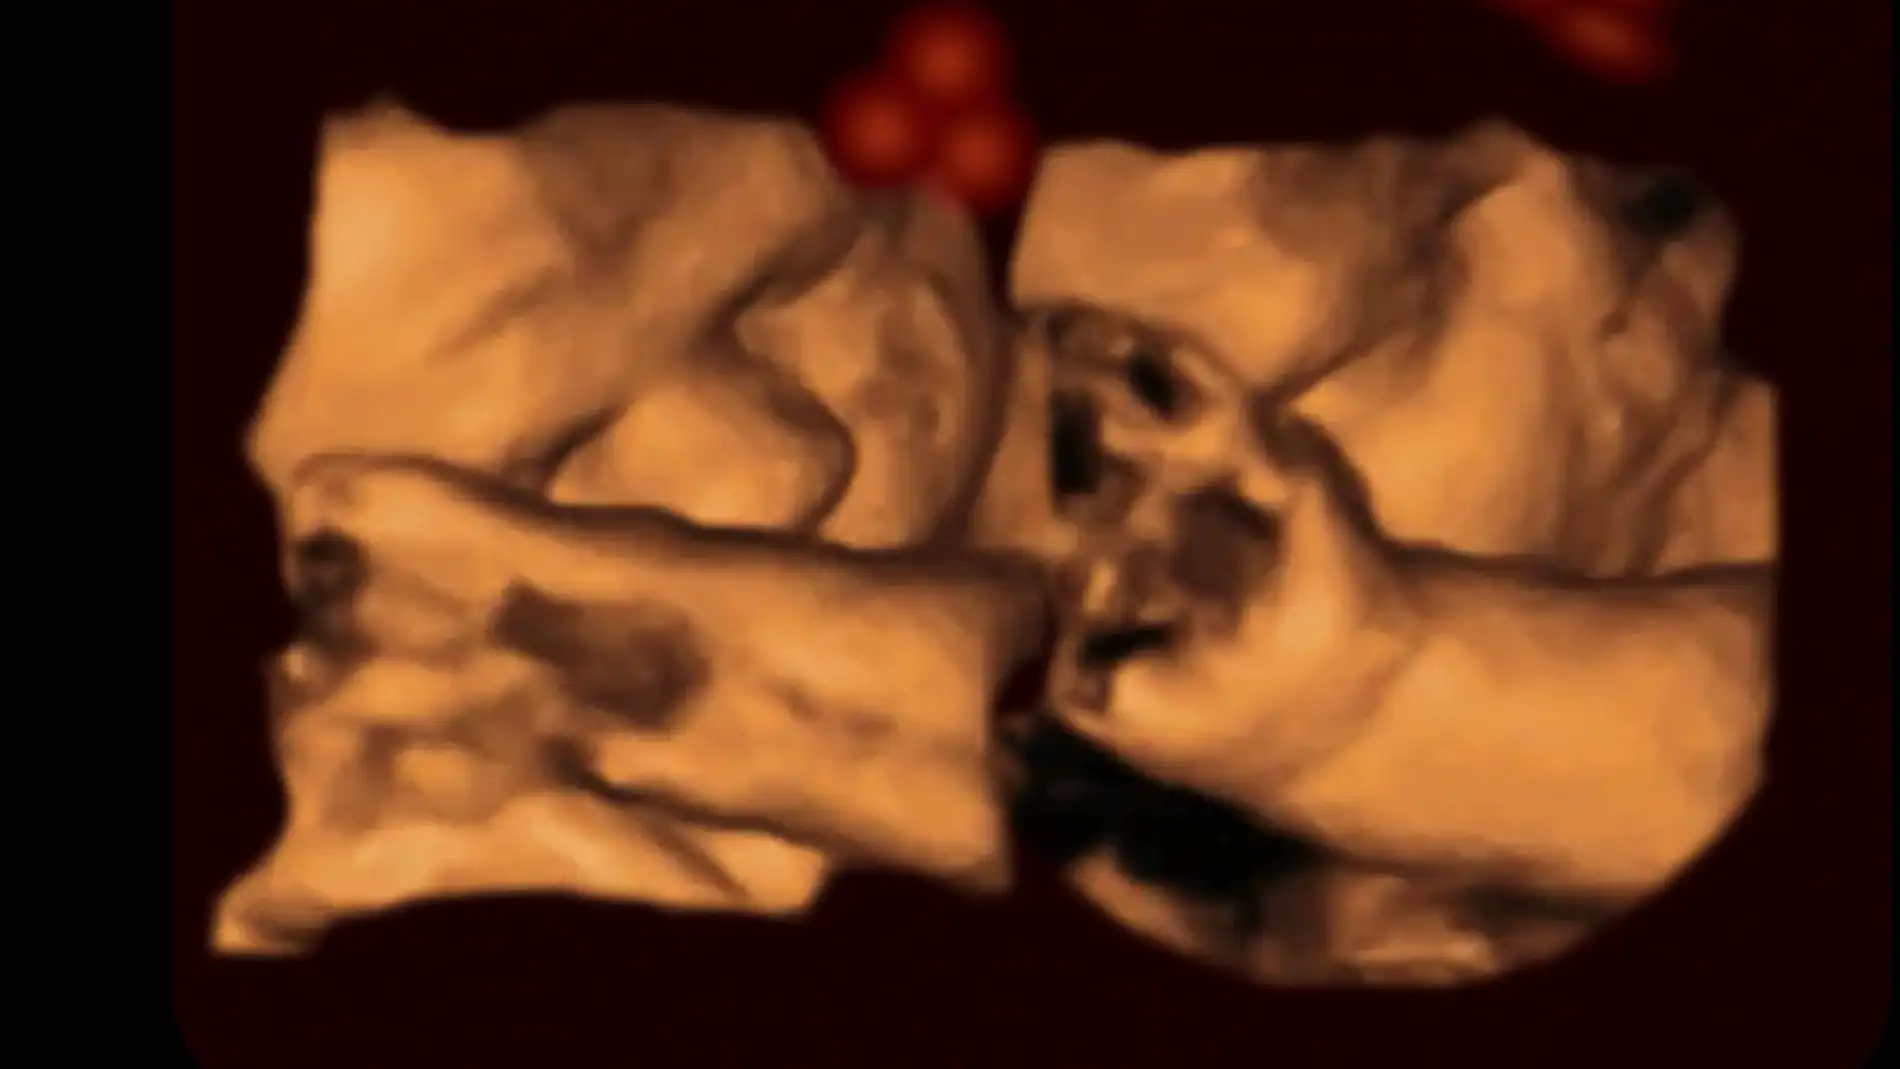

Dispositivo de ultrasonido 4D

Hasta el momento, otros estudios no habían podido observar las reacciones del feto frente a estímulos concretos, debido a cuestiones técnicas. Ahora los cientíticos han utilizado un dispositivo de ultrasonido 4D de alta calidad para estudiar su comportamiento.

Para realizar este estudio, los investigadores han analizado las repuestas de 39 fetos ante figuras lumínicas con formas de caras, proyectadas con distintas orientaciones. Las luces emitidas las movían a través de sus campos de visión, mientras observaban con el ultrasonido 4D sus reacciones.

Las películas obtenidas muestran que los bebes se sentían más atraídos por los rostros ‘normales’, que por los invertidos. Con estos resultados, los autores sugieren que los bebes adquieren antes del nacimiento la capacidad para reconocer caras. Además, han comprobado que la luz exterior puede atravesar los tejidos humanos y llegar al útero.